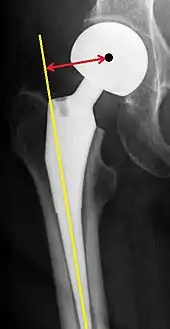

Hip prosthesis displaying aseptic loosening (arrows)

Hip prosthesis zones according to DeLee and Charnley,[29] and Gruen.[30] These are used to describe the location of for example areas of loosening.

On radiography, it is normal to see thin radiolucent areas of less than 2 mm around hip prosthesis components, or between a cement mantle and bone. These may indicate loosening of the prosthesis if they are new or changing, while areas greater than 2 mm may be harmless if they are stable.[31] The most important prognostic factors of cemented cups are absence of radiolucent lines in DeLee and Charnley zone I, as well as adequate cement mantle thickness.[32] In the first year after insertion of uncemented femoral stems, it is normal to have mild subsidence (less than 10 mm).[31] The direct anterior approach has been shown to itself be a risk factor for early femoral component loosening.[33][34][35]